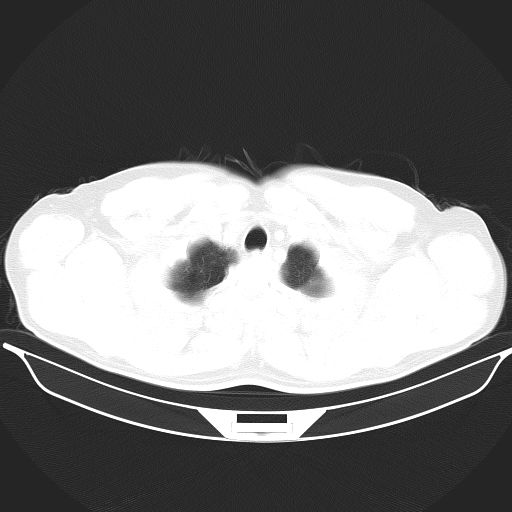

标题: CT25490:男,40岁,体检发现;无其它不适。 [打印本页]

标题: CT25490:男,40岁,体检发现;无其它不适。

考虑右下肺周围性肺癌并肺内多发转移,纵隔淋巴结转移!

支持 !考虑右下肺周围性肺癌并肺内多发转移,纵隔淋巴结转移,(气管前腔静脉后,隆突下,主动脉弓下都有了)